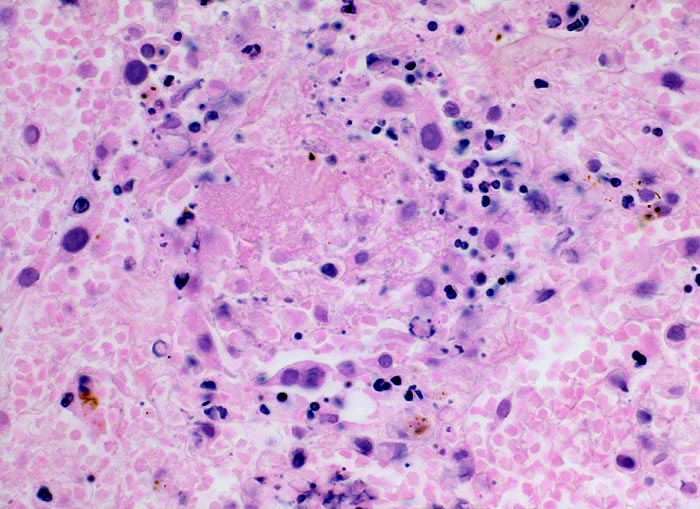

hämorrhagischer Lungeninfarkt

vaskulär / Durchblutungsstörung

Lunge

Das Lungengerüst ist nur noch schattenhaft erkennbar. Die Kerne von nekrotischen Typ II Pneumozyten sind stark abgeblasst. Von anderen Zellen sind nur noch Kerntrümmer erkennbar. Die Alveolen enthalten reichlich Blut und Fibrin.

Tiefe Beinvenenthrombosen bei metastasierendem Prostatakarzinom. Koronare Herzkrankheit.

400